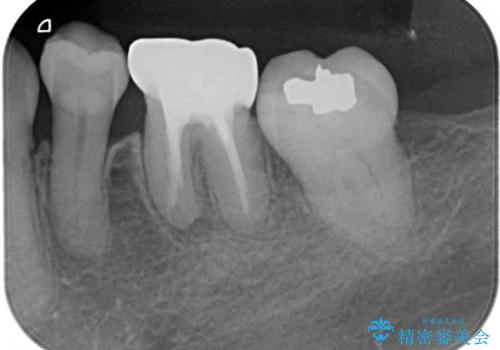

- 矯正治療後に、下顎奥歯の銀歯をすべてゴールドにすることを希望された患者様です。

セラミッククラウンやセラミックインレーによる補綴治療も提案しましたが、お友達にゴールドを自慢したいとのことで、ゴールドクラウンとゴールドインレーにて処置することとしました。